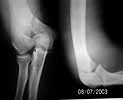

This boy 16y has this fracture. i think its 13B2.2.

what best way for fixation\Y-plate, screws, plating....etc